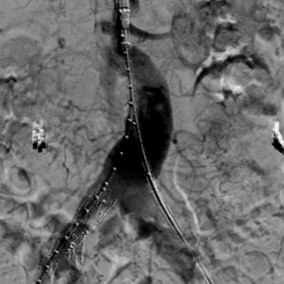

术中行右侧髂内动脉IBD及腹主动脉-双侧髂动脉瘤支架隔绝

术后半年复查CT显示腹主动脉-双侧髂动脉瘤完全隔绝,右侧髂内动脉血流通畅。